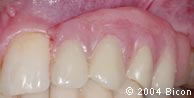

74. | 一体化基台冠完全就位后的颊侧观。 |

75. | 一体化基台冠完全就位后的颊侧观。 |

76. | 一体化基台冠完全就位后的颊侧观。 |